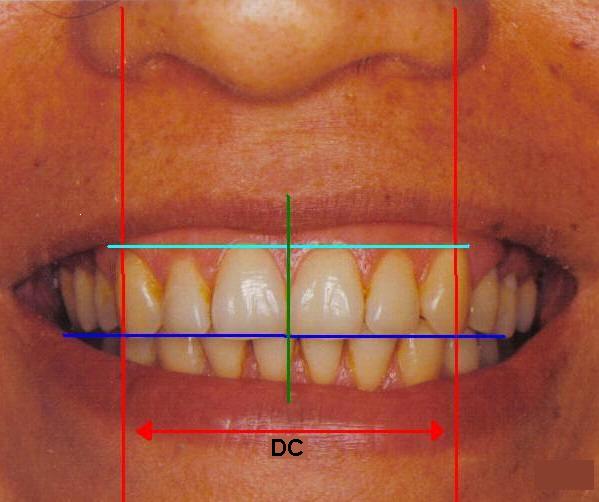

4- Con el paciente mordiendo suavemente los

rodetes marque las referencias necesarias para la elección de los

dientes:

- La línea media, (en color

verde) Ver fotografías y gráfico derecha

- Líneas caninas, (en

color rojo) es la línea perpendicular al plano de oclusión

que pasa por el borde externo del ala de la nariz de nuestro

paciente y por ende la distancia "ínter canina

o DC" que nos determinará el ancho

de los dientes anteriores, medida desde las cúspides de los caninos.

- También puede marcar en el rodete de mordida la ubicación de

las comisuras de los labios, con la boca cerrada, la cual determinará la distancia de

los dientes anteriores, medidas desde distal de canino a canino.

- Línea de los cuellos dentarios.

(en color celeste)

- Solicite al paciente que sonría, y marque la línea de los

cuellos dentarios en el rodete, o también "mal llamada línea de

la sonrisa"

- Plano oclusal.

(en color azul)

- La distancia entre la línea de los cuellos dentales y el plano

oclusal nos determinará el alto de los dientes antero superiores

|